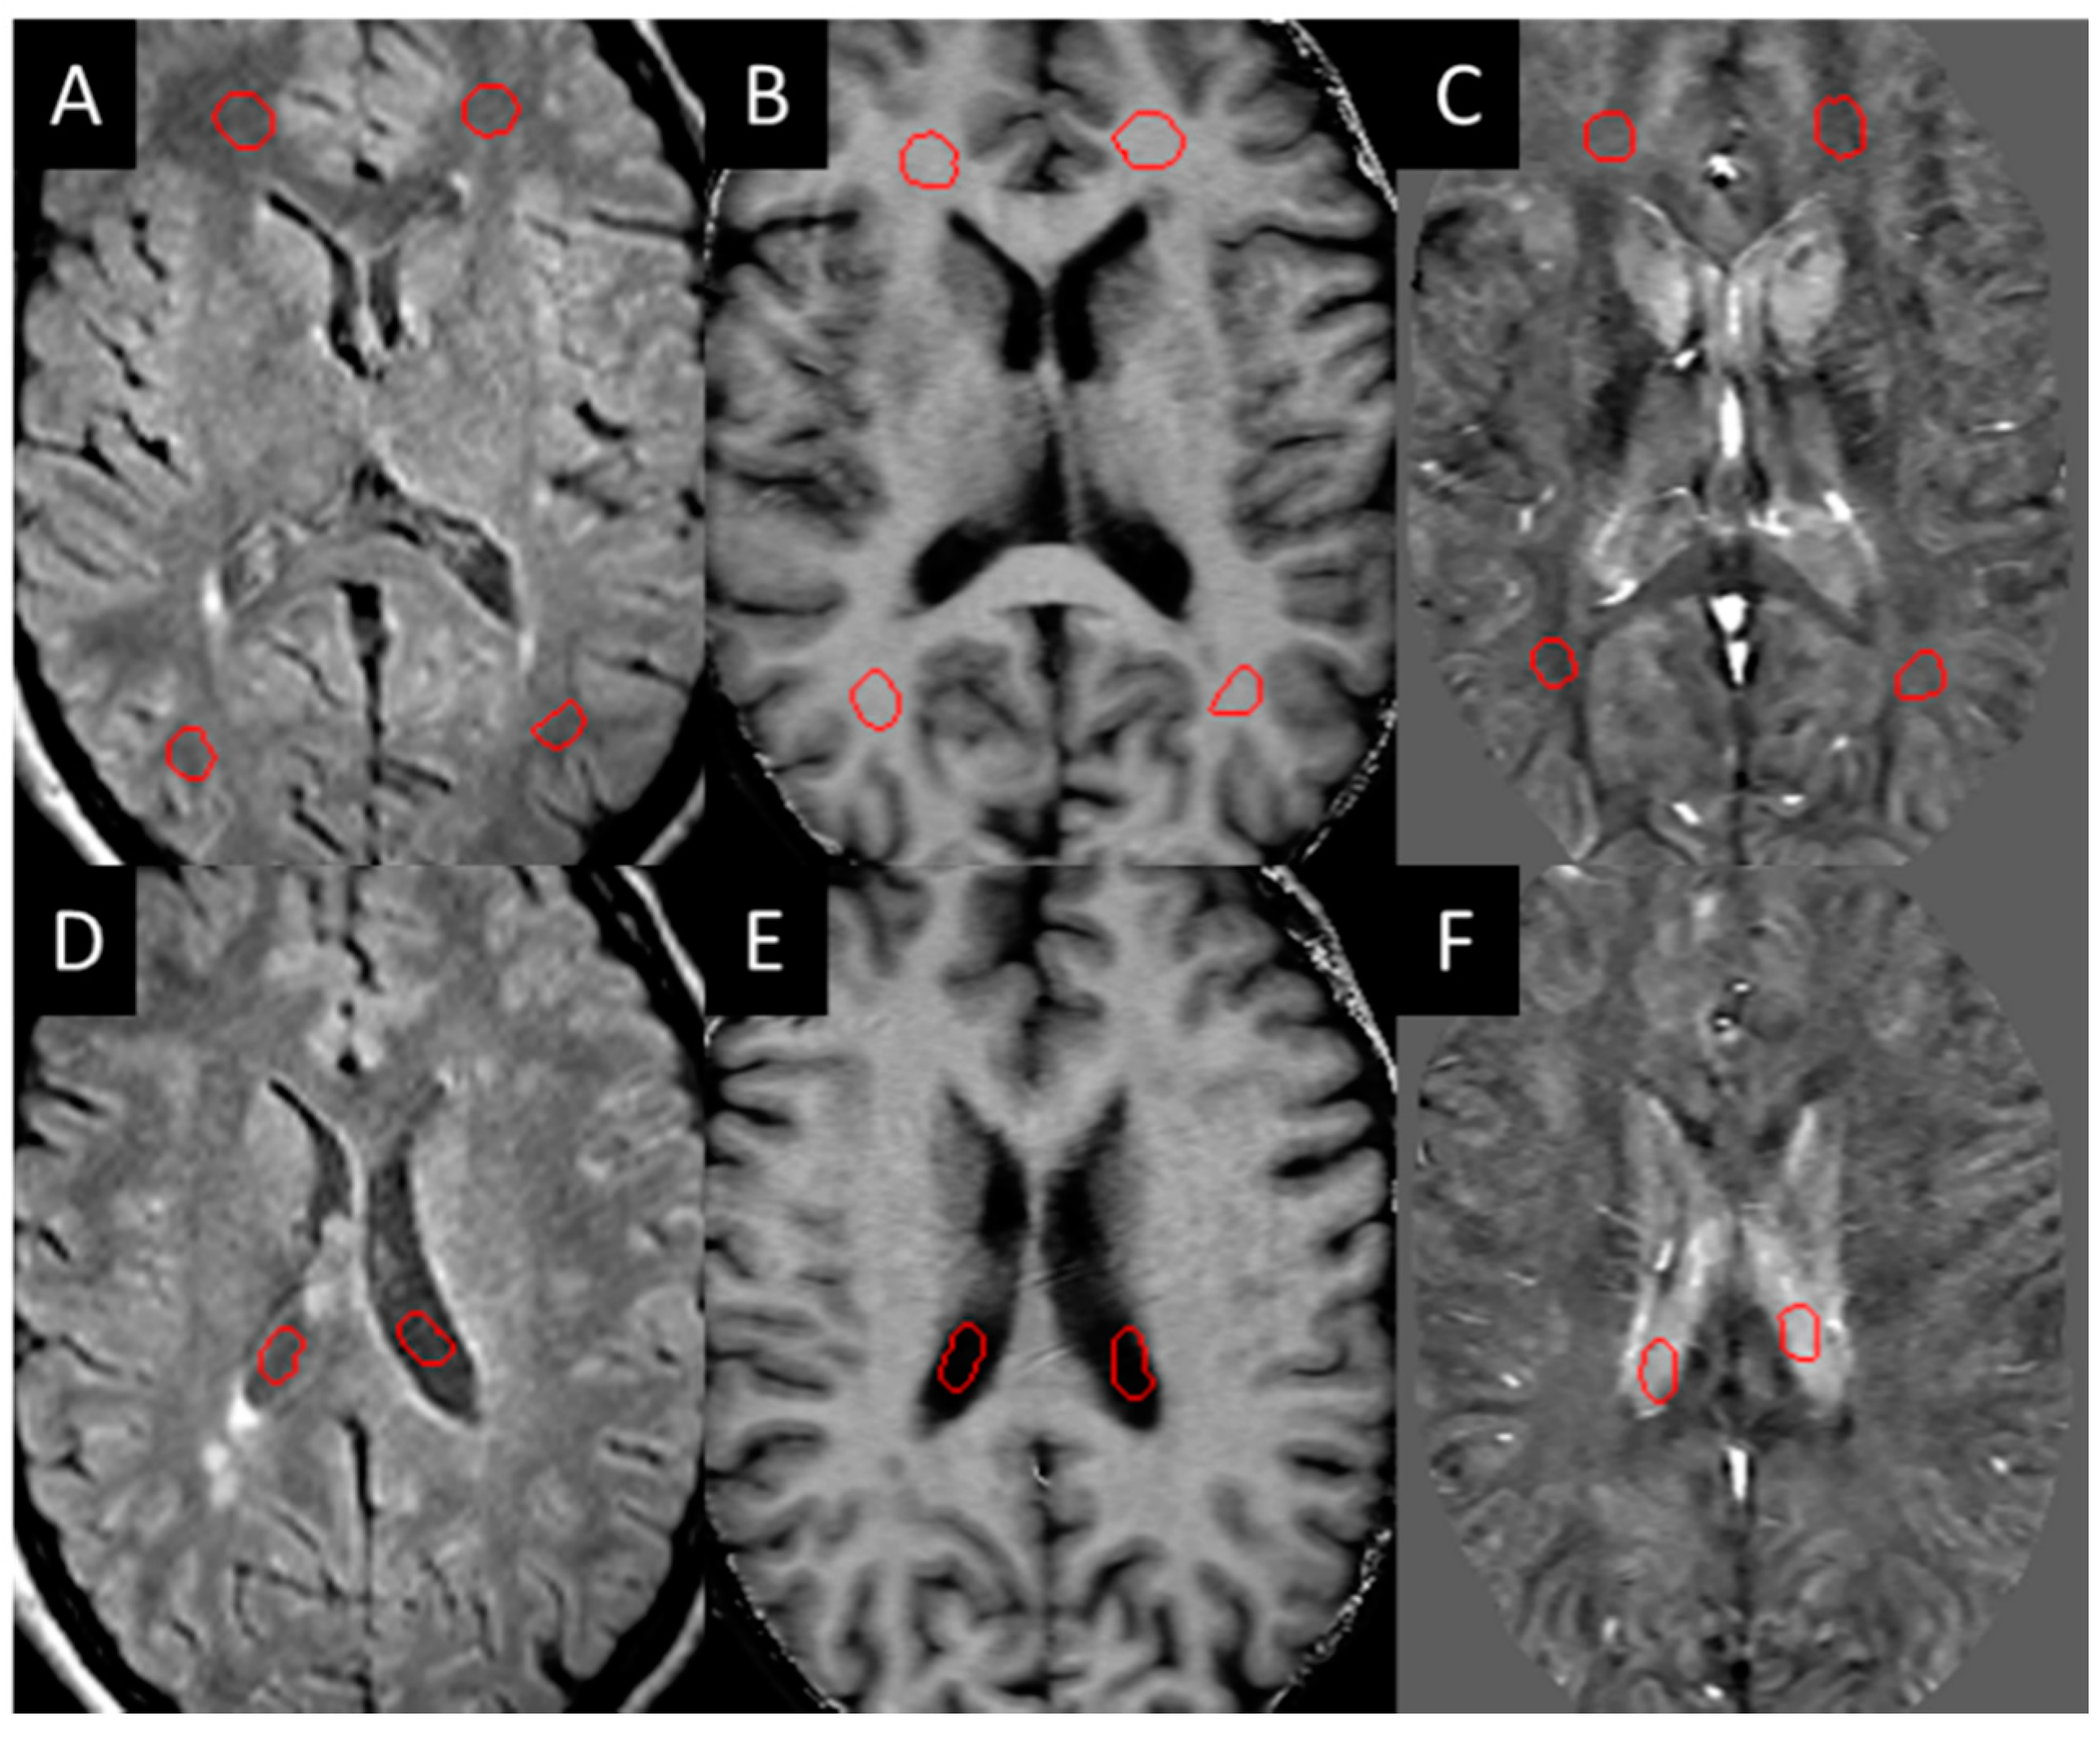

Three-dimensional T2 FLAIR images were evaluated for white matter hyper-intensities (WMH), which were quantified into lesion load using a semi-automated tool (SPIN software, SpinTech Inc., Bingham Farms, MI, USA) and later confirmed by a radiologist. All the lesions were then evaluated for their appearance in QSM and SWI high-pass filtered phase data in the baseline images. Those that could be visually observed (positive susceptibility) compared to the surrounding white matter were manually drawn as a lesion region of interest (ROI) and classified as QSM positive (QSM+) lesions. These lesions were then manually drawn according to the contrast in each modality (the ROIs were not copied between each modality as the appearance of the lesion varied between each modality). Normal-appearing white matter (NAWM) regions of the same size were then drawn on the contralateral side of the brain across different slices as close to being symmetric with the lesions as possible. NAWM ROIs were also drawn in the healthy control sampling four different regions in both hemispheres within the frontal, temporal, and parietal lobes (Figure 1).

Figure 1.

Example of NAWM ROIs (red circles in A–C) drawn on the white matter and in the CSF (red circles in D–F) for test re-test reliability: (A,D) T2 FLAIR, (B,E) MTR, (C,F) iSWIM.